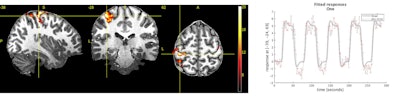

The scanner features a 60-cm bore, which is particularly effective for neurodegenerative disease imaging and extremities, as well as the company's UltraG gradient technology. It also includes GE's SignaWorks applications platform with AIRx for automated slice positioning and GE's Silent Scan imaging technology.

The Magnus gradients are being used in a head-only device for a study conducted by GE's Research Center and Uniformed Services University (USU) and funded by the U.S. Department of Defense. The study will test military personnel with acute and chronic mild traumatic brain injury.

The Magnus gradients perform in the 500 to 700 tesla/meter/second (T/m/s) and 200 to 300 millitesla/meter (mT/m) range compared with ranges of 200 T/m/s and 50 to 80 mT/m found in conventional scanners, GE said.